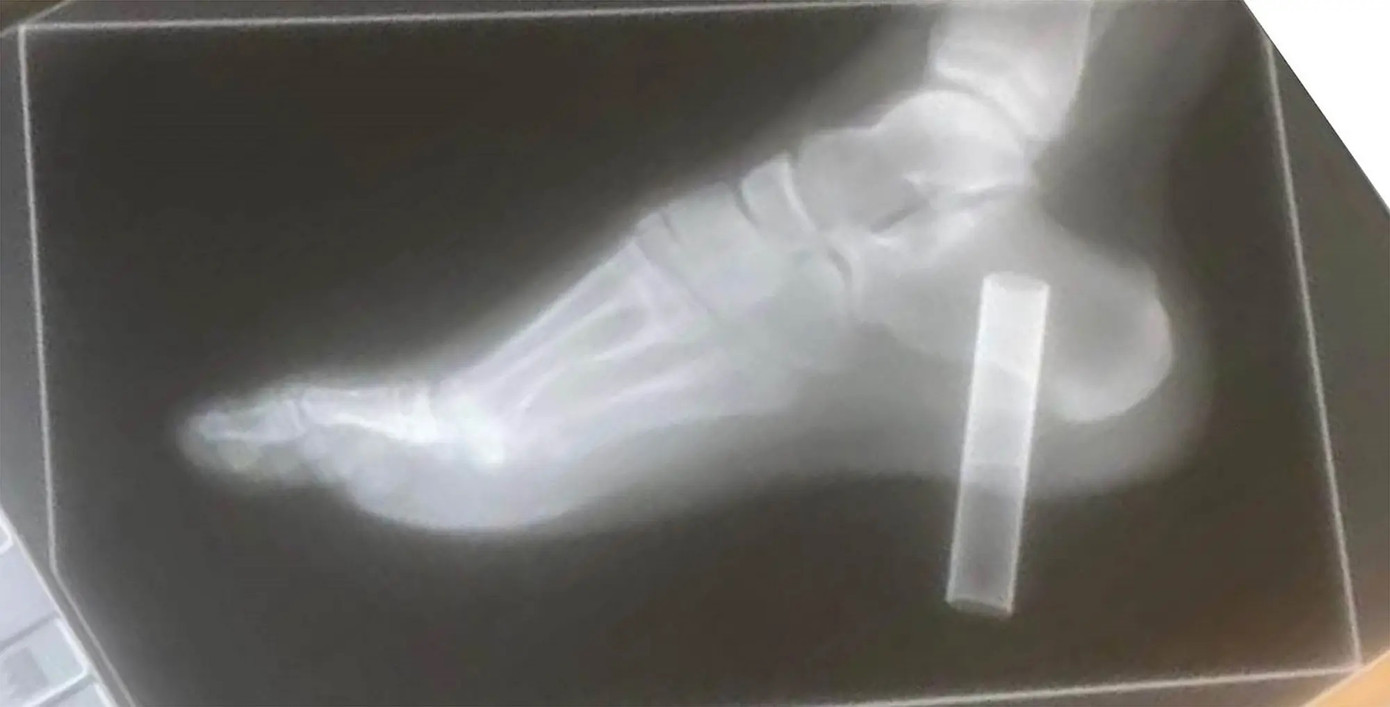

| Hỉnh ảnh X-quang cho thấy thuốc lá điện tử cắm vào lòng bàn chân của anh ấy |

Do vết thương quá nghiêm trọng, Bennett phải chuyển đến khu cấp cứu tại Bệnh viện Hoàng gia Gloucester, nơi cậu được tiêm thuốc kháng sinh và thuốc giảm đau. Các lần chụp X-quang sau đó cho thấy điếu thuốc lá điện tử đã xuyên sâu vào xương gót chân của cậu.